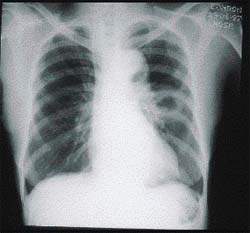

Симптомы и признаки туберкулеза: как распознать заболевание

Раздел: Визуальные уроки